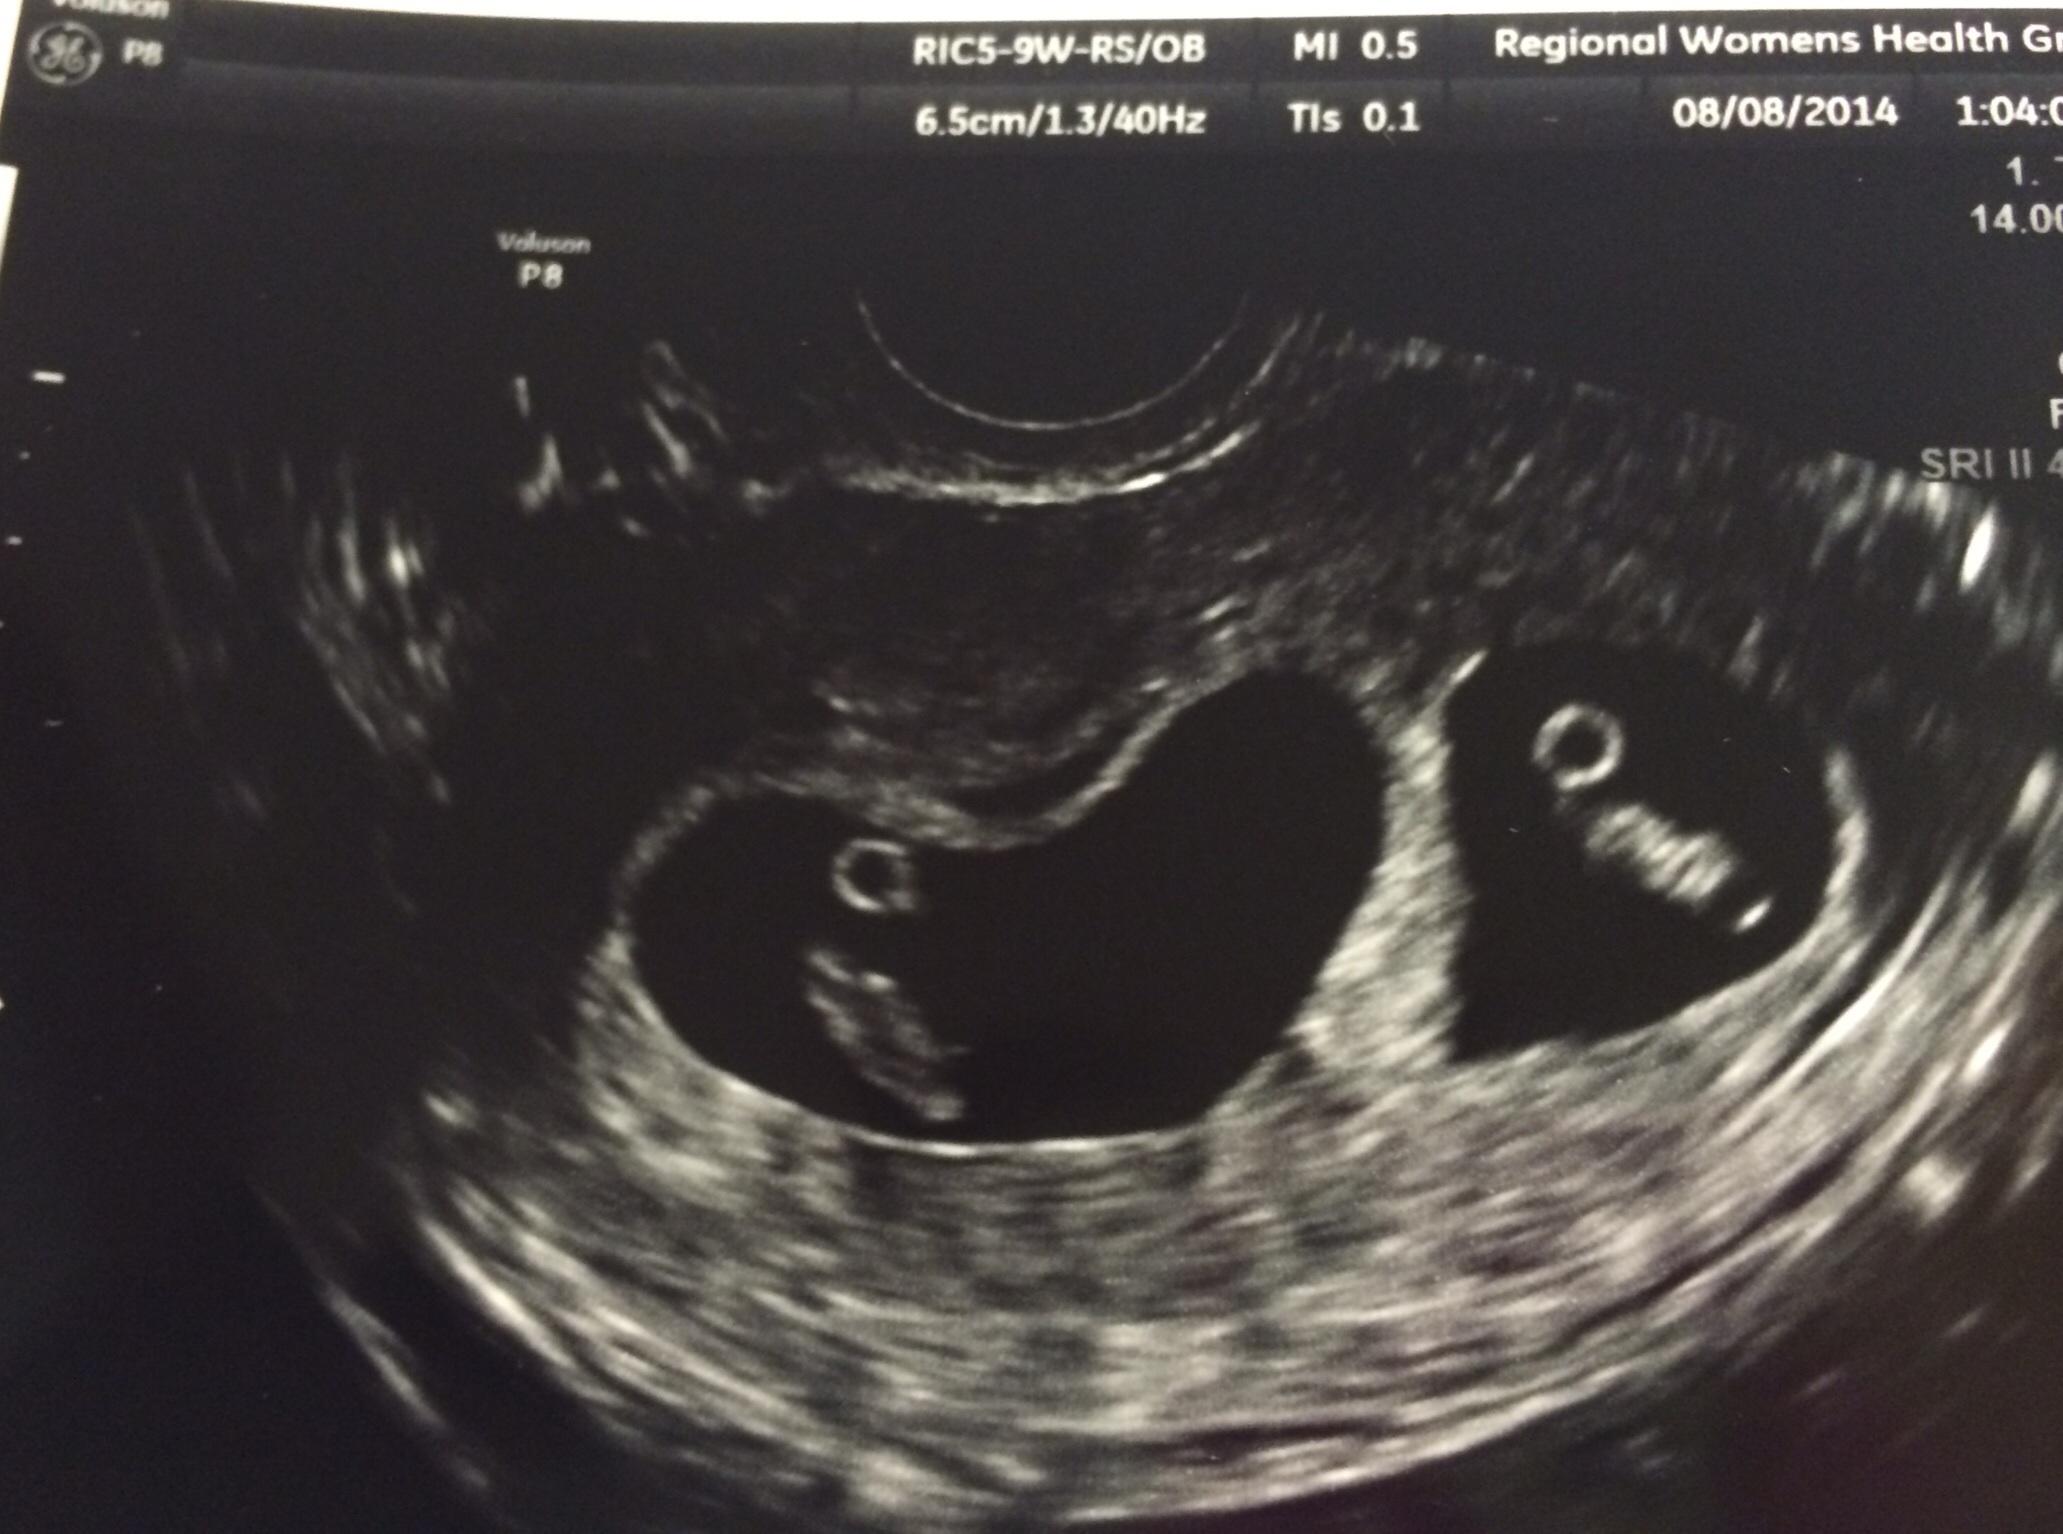

DH and I went to our first US yesterday and found out that we're having fraternal twins!! Anyone else in the same boat?!? So excited but freaking out lol!!! Hoping one is a boy and one is a girl!! Fingers crossed!